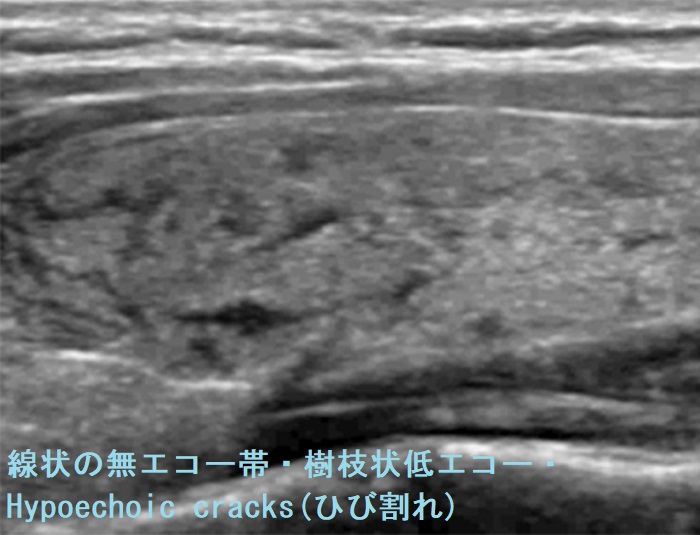

- 線状の無エコー帯/樹枝状低エコー/Hypoechoic cracks(ひび割れ)

(ドプラーで血流乏しく、エラストグラフィーで軟らかい):おそらく穿刺刺激により、何らかの血管透過性物質が放出されたためと推察されます。 -

甲状腺穿刺細胞診自体はうまく行ったのに直後(1-3分後)から数時間後、急激な穿刺部の痛みと甲状腺腫脹(急性反応、急性一過性甲状腺腫大)がおこる。穿刺刺激により血管透過性物質(サブスタンスP やニューロキニンA などのタキキニン)が放出された可能性。穿刺時出血と鑑別要。超音波エコー画像所見は甲状腺腫大、前頚筋腫大と線状の無エコー帯/樹枝状低エコー/Hypoechoic cracks(ひび割れ)(ドプラーで血流乏しく、エラストグラフィーで軟らかい)を。治療は、念のため入院し局所冷却、ステロイド点滴静注(メチルプレドニゾロン125-250mg程度)。

- 褐色細胞腫の高血圧発作時;痛みはない。急激な甲状腺びまん性腫脹と樹枝状低エコー(線状の無エコー帯)[一過性甲状腺腫大(発作性甲状腺腫脹)]

- 甲状腺のう胞内出血で、同側あるいは反対側の甲状腺内に樹枝状低エコー/Hypoechoic cracks(ひび割れ)が出現